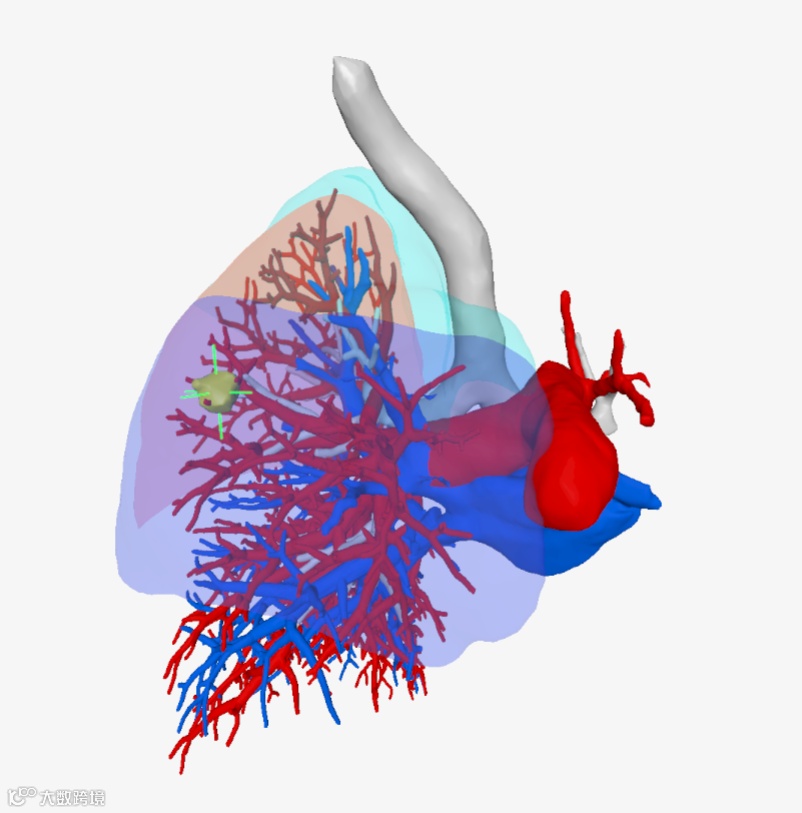

▲▲▲三维重建支气管

▲▲▲三维重建血管

该院胸外科手术团队用瀚依科技的AI三维重建服务,真实还原了结节的大小、位置和深度,全方位、多维度地观察了患者结节的空间位置、结节与周遭脏器粘连程度、结节对血管的侵占情况,并对手术需要的重要信息进行精准定量分析。